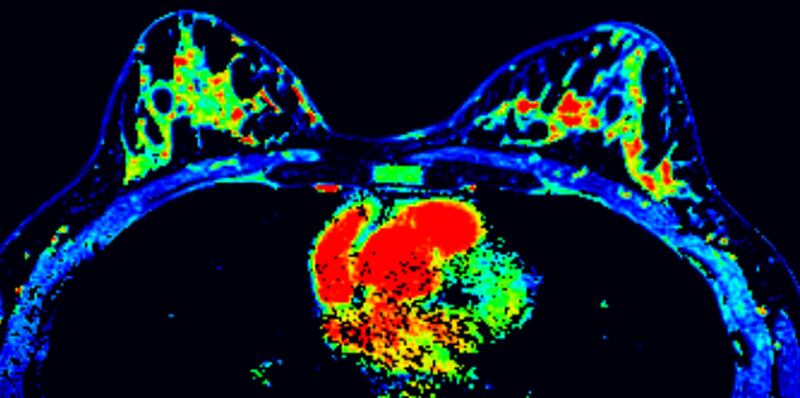

“Una mamografía es una imagen de la mama tomada con rayos X que permite ver una imagen del interior de los senos. Existen mamografías de detección y mamografías de diagnóstico. Al realizarse una mamografía como especialista puedo detectar irregularidades en la mama o tumores que aún no se pueden sentir”, cuenta Clayreth Vinueza especialista en radiología.

“Una ecografía de mama es una técnica de imagen y prueba complementaria a la mamografía que examina los senos mediante ultrasonidos y sirve para realizar una evaluación completa de masas que se pueden palpar pero que no aparecen en las mamografías. La ecografía mamaria permite ver las diferencias entre nódulos sólidos (tumor) y nódulos líquidos (quiste) esto influye entre las condiciones en las que se pueda encontrar el tumor ya sean benignas o malignas”, explicó la Dra. Vinueza.